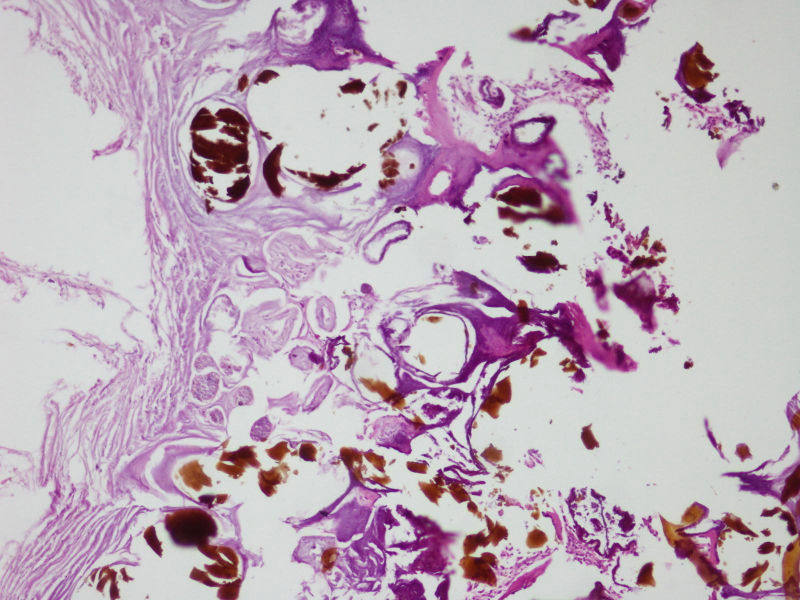

网膜结节

图1

图2

图3

图4

图5

图6

图7

图8

图9

图10

寄生虫卵?

应该是钙皂,有无慢性胰腺炎?